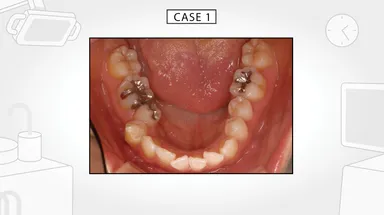

今回発表した動画は、それらの不定愁訴を引き起こしている原因が口内の舌の緊張によるものであることを示し、さらに、その要因は現代人の食生活が引き起こした顎や歯に見られる身体的特徴ということを解説しています。